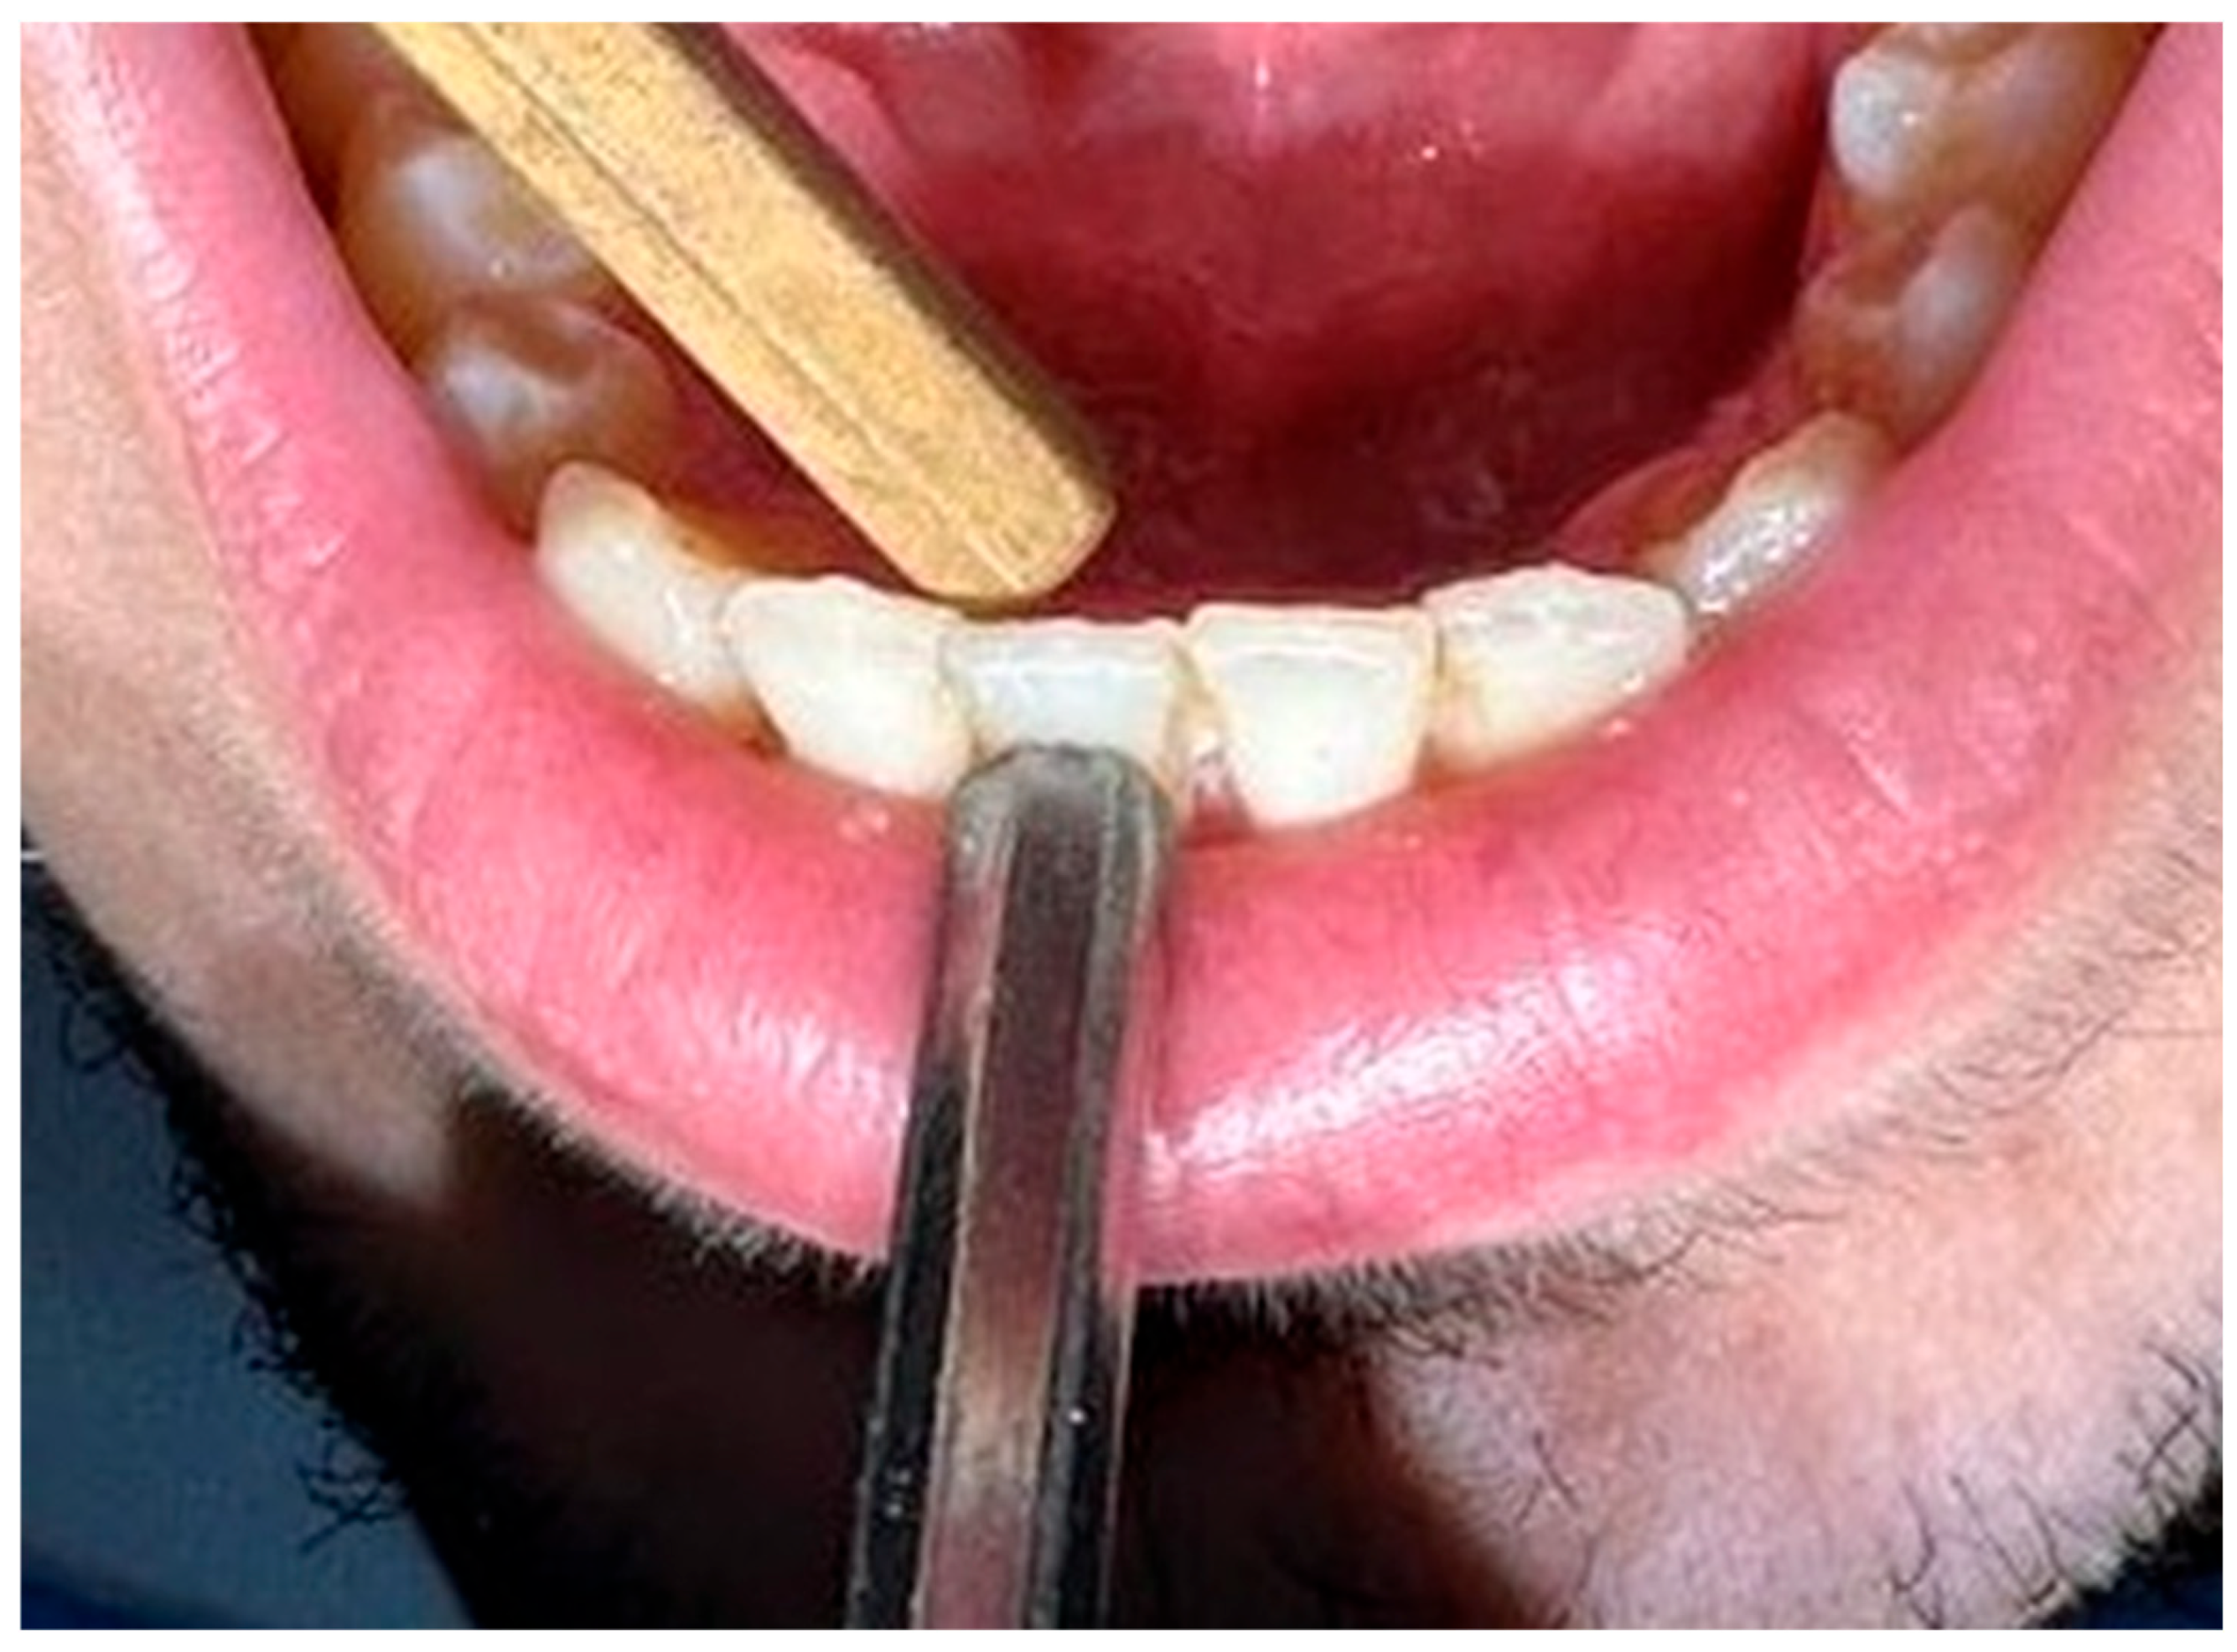

2. Materials and Methods